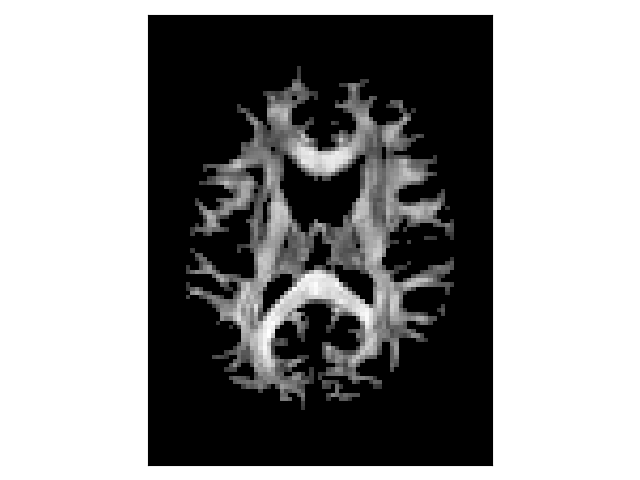

A scalar map can be used to define where the tracking stops. The threshold stopping criterion uses a scalar map to stop the tracking whenever the interpolated scalar value is lower than a fixed threshold. Here, we show an example using the fractional anisotropy (FA) map of the DTI model. The threshold stopping criterion uses a trilinear interpolation at the tracking position.

threshold_criterion = ThresholdStoppingCriterion(FA, 0.2)

fig.savefig("threshold_fa.png")

tracking stopping criterion

Thresholded fractional anisotropy map.